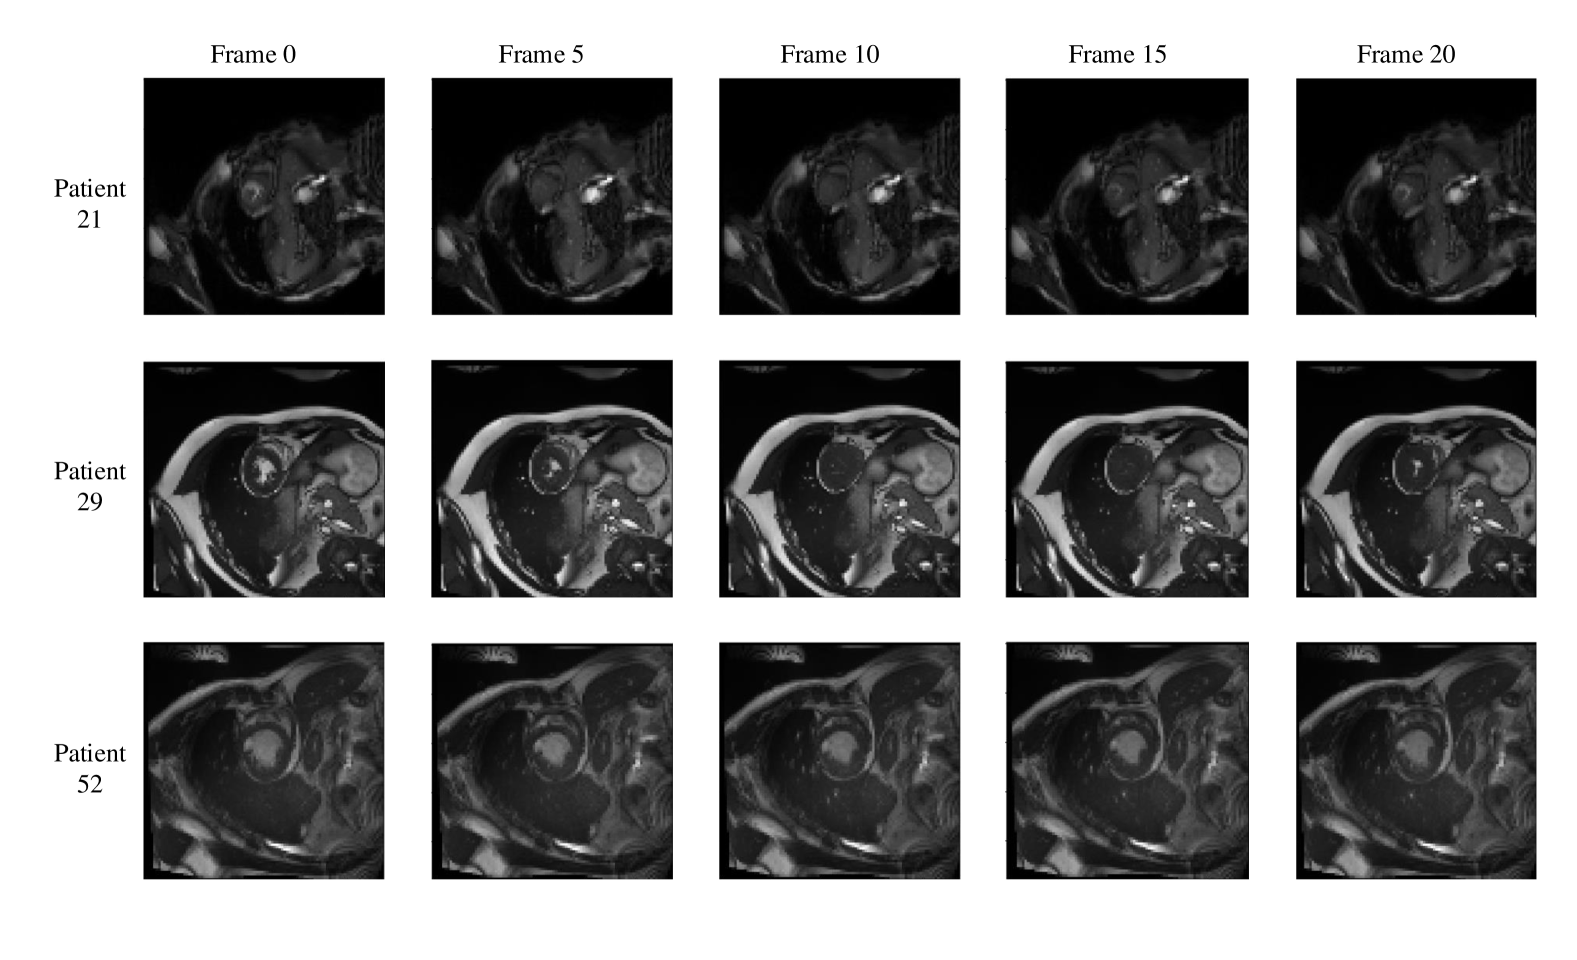

Refer to caption

Figure 7: Frames of CMR sequence from three patients. Note the brightness heterogeneity in LV and RV on the first few frames. Using LSTM as decoder, the model can get more temporal information from the previous and future frames and result in more accurate segmentation.

3.3 Bi-directional Training

We notice that the prediction results of myocardium segmentation in CMR image is highly related to the segmentation result of frames either behind or after it. The first frame of CMR sequence will not receive enough information if we only use forward Conv LSTM. Figure 7 shows some frames of CMR image of different patients in the ACDC dataset. We can see that the frames of CMR image of the last frame is highly related to the image of the next frame. Consequently, the prediction error of the first frame due to the brightness heterogeneity may propagate to the rest of the CMR frames.

Therefore, we adopted a bi-directional training approach to alleviate this problem. Specifically, we used two Conv LSTMs in our decoder model. One will propagate forward, from frame 1 to frame T𝑇T, while the other will propagate backward, from frame T𝑇T to frame 1. T𝑇T is the total number of frames in one CMR sequence. Figure 5 presents the workflow of proposed bi-directional training approach. Such approach can better exploit the temporal information along the frames thus improve the segmentation accuracy.